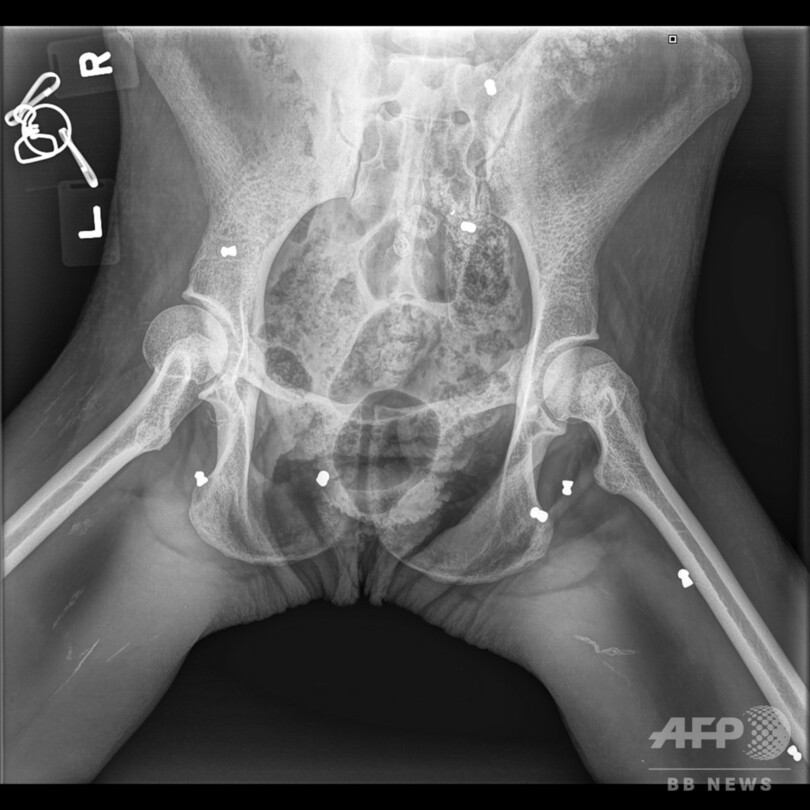

同国アチェ(Aceh)州当局は今月10日、村民の通報を受け、重傷を負った30歳の雌のオランウータンを発見した。オランウータンは、村民の一人が所有する農園内のジャックフルーツの木の下で死にそうな状態になっていた。このオランウータンの生後1か月になる赤ちゃんも一緒に見つかった。当局はすぐに2匹を保護したものの、赤ちゃんは栄養不良で死んだ。

同州自然資源保護事務所(BKSDA)のサプト・アジ・プラボウォ(Sapto Aji Prabowo)氏は、「農園に来たオランウータンに脅威を感じた所有者が、オランウータンを追い出そうと試みた」と説明した。保護から1週間が経過し、「ホープ(希望)」と名付けられた母親のオランウータンは少しずつ回復している。サプト・アジ・プラボウォ氏はAFPに対し、「ホープは回復してきており、食べ物も食べ始めた」と語った。